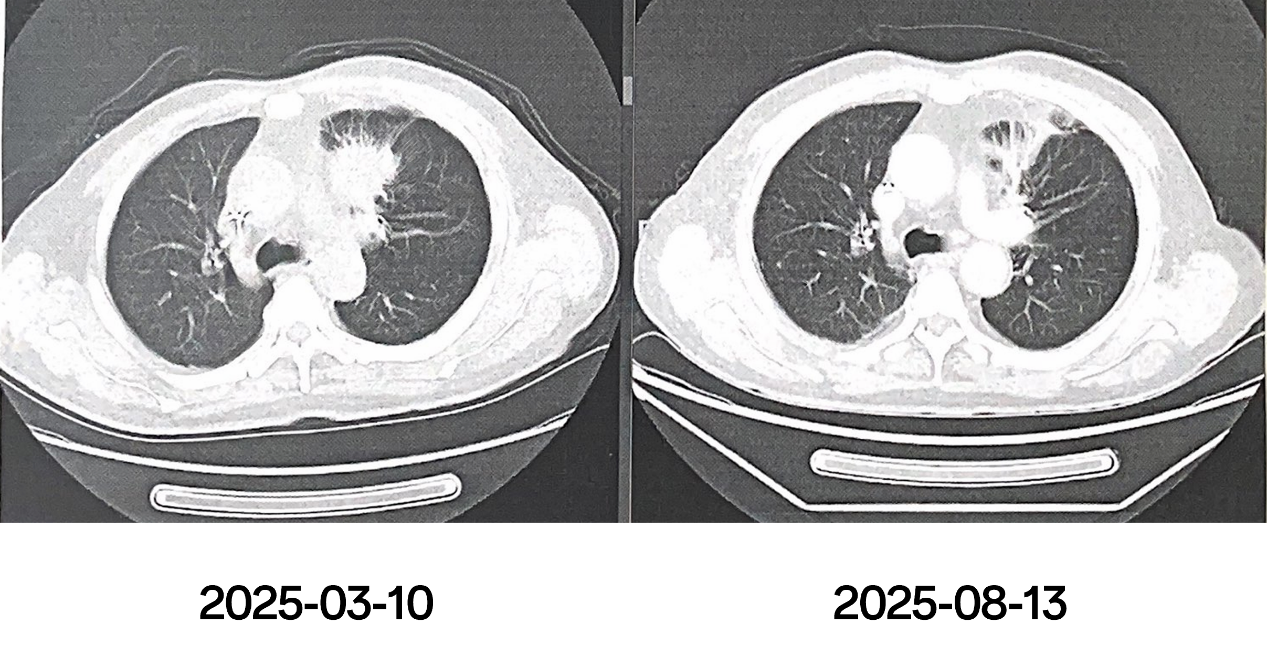

2025-07-28患者复查CT提示右肺中叶结节较前增大,上叶新发病灶。遂于我院就诊。

2025-08-06至2025-08-26,排除放疗禁忌后,行姑息性放疗,具体:肺上叶、中叶转移灶:60Gy/15FX,4Gy/FX,放疗期间联合甘氨双唑钠放疗增敏,予以雾化吸入止咳化痰,保肝等对症治疗。

2025-09-23,放疗后1月,复查胸部CT:左肺术后改变,请结合临床病史。左肺胸膜下多发结节、钙化灶。右肺上叶结节,对比前片未见明显改变。右肺上叶多发磨玻璃结节。右肺中叶结节,对比前片略小,肺气肿、肺大泡。左侧胸膜及肋骨改变,主动脉及冠状动脉硬化性改变。

2025-11-26,放疗后3月,复查胸部CT:左肺术后改变,请结合临床病史。左肺胸膜下多发结节、钙化灶。右肺上叶结节,右肺中叶结节对比前片未见明显改变。肺气肿、肺大泡。左侧胸膜及肋骨改变,主动脉及冠状动脉硬化性改变。